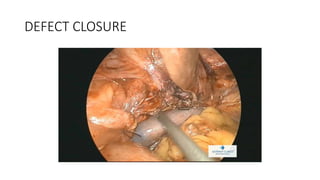

DEFECT CLOSURE

DEFECT CLOSURE AND MESH PLACEMENT